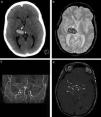

Paciente con cefalea y hematoma en la región tálamo capsular derecha. Se observa (a) en la TC una lesión espontáneamente densa (flecha) y (b) en la secuencia GRE, corte axial, un área de hipointensidad (flecha). (c) La angio-RM tridimensional TOF registra ausencia de señal en los tramos terminales de ambas carótidas internas (puntas de flecha), mientras que (d) en los cortes axiales crudos se identifican pequeños vasos colaterales en las arterias comunicantes posteriores y en ambas arterias cerebrales posteriores, hallazgos correspondientes a enfermedad de moyamoya en estadio III (flechas).